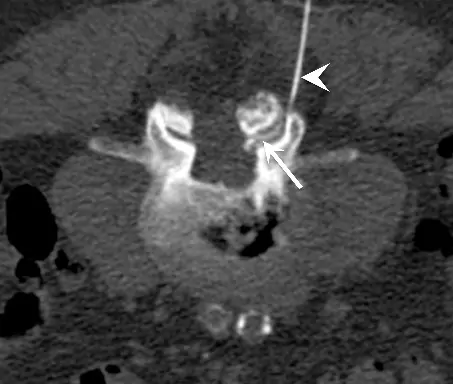

We perform USG and CT guided injections and blocks for pain management, including procedures such as epidural injections, facet blocks, suprascapular nerve blocks, etc.

Siemens Definition CT Scanner with TwinBeam with Flouroscopy